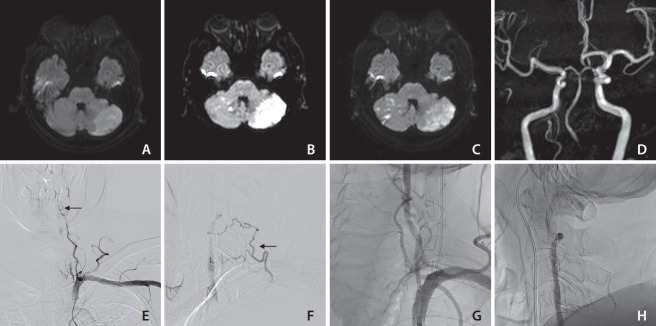

Vertebral artery stump syndrome (VASS) is a rare condition that can cause posterior circulation ischemic stroke due to occlusion of the ipsilateral vertebral artery (VA) orifice, resulting in blood flow stagnation and embolus formation. Although there is no established treatment for this condition, we observed 3 cases of VASS out of 326 acute ischemic stroke cases at a single institution from April 2021 to October 2022. Despite the best possible antithrombotic treatment, all 3 patients had recurrent ischemic strokes. One patient underwent drug-eluting stenting of the VA orifice to relieve occlusive flow. The other 2 patients received coil embolization, which resulted in the disappearance of their culprit collateral flow. None of the patients had recurrent ischemic strokes after endovascular intervention. Based on our observations, stenting and coil embolization are effective methods for preventing future recurrences of VASS.

Abstract Image